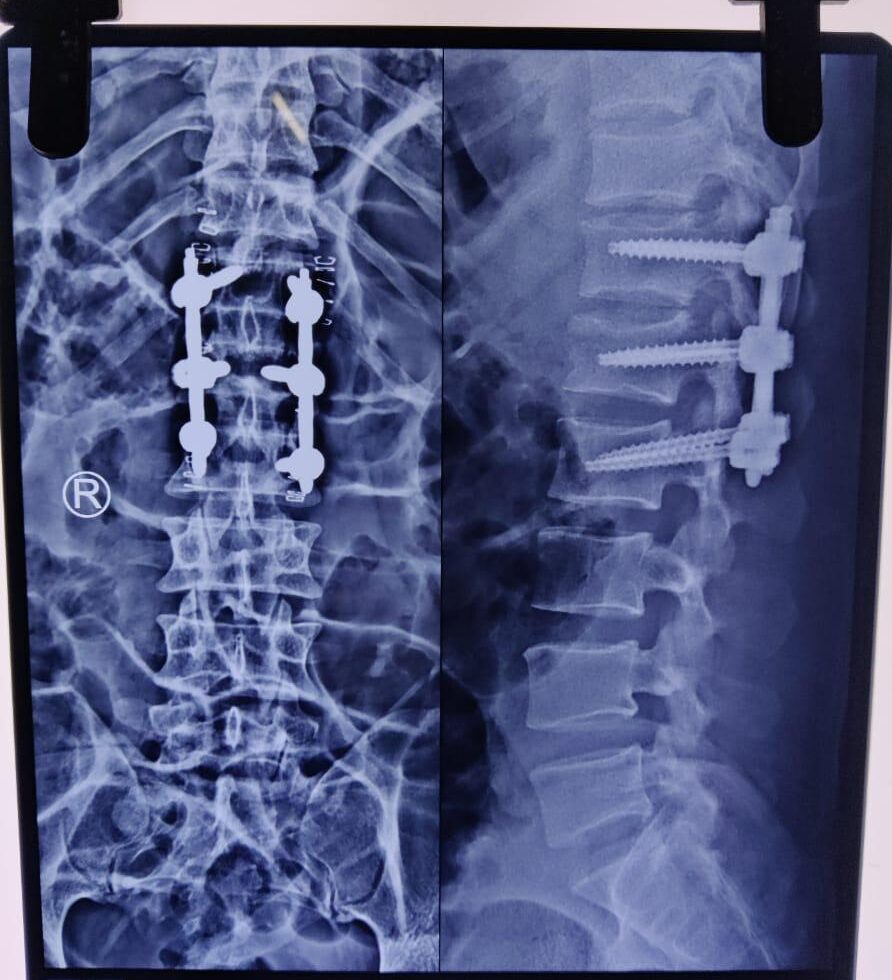

Moments That Mark Meaningful Recovery

Witness real patient transformations at The Ortho Clinic through images that reflect successful treatments and restored mobility.